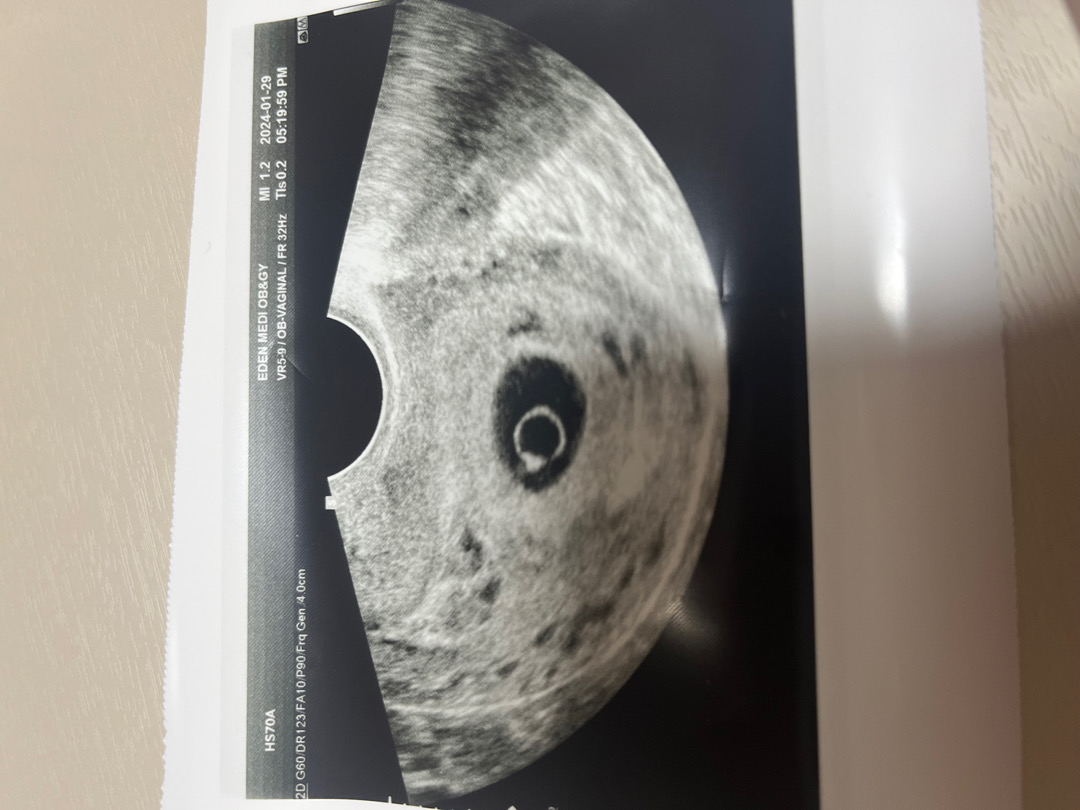

6주차 심장소리

병원에서 주차수나 아기집에 비해 난황이 너무 크고 아기 심장소리가 너무 미약해서.. 좀 지켜봐야 한다고 하시는데요 보시기에 어떠신가요.. 유산 방지 주사나 어떤게 도움이 될까요.. 너무 슬프고 무기력해요